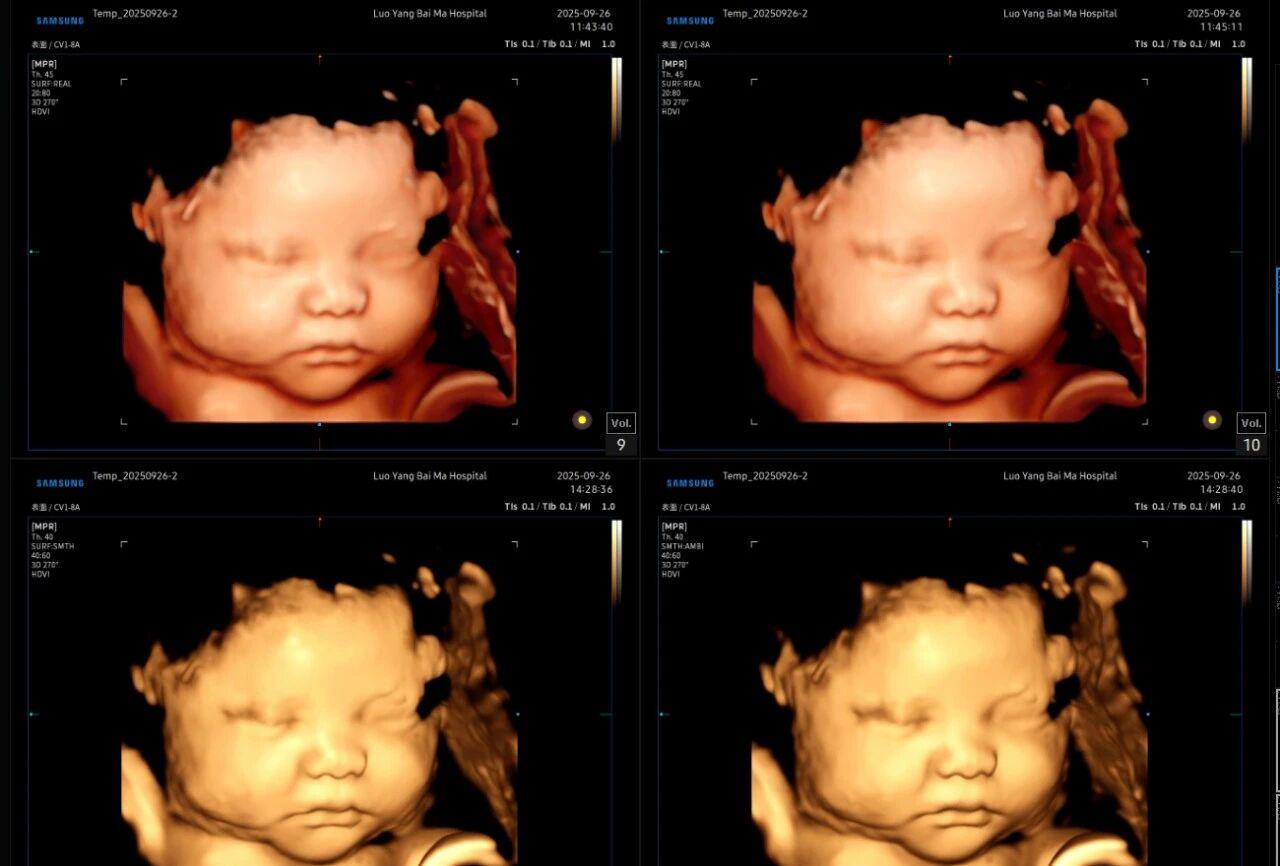

很多准妈妈可能对四维(4D)彩超已经非常熟悉,它能够实时动态地展示宝宝在宫内的活动,让我们看到宝宝打哈欠、伸懒腰的可爱模样,为无数家庭留下了珍贵的第一份“动态影集”。

那么,5D彩超又是什么呢?“5D”中的“第五维度”,并非指传统意义上的空间维度,而是代表着“智能(Intelligence)”与“数据(Data)”的深度融合。它是在4D实时动态成像的基础上,引入了先进的AI人工智能辅助分析技术。如果说4D彩超是为我们拍摄了一部关于宝宝的“现场直播电影”,那么5D智能彩超则像一位经验丰富的“智能剪辑师”,能够自动捕捉关键信息,并进行精细化、多维度的分析与呈现。

5D智能彩超拥有更高的分辨率和更强的图像处理能力,能够呈现出接近“IMAX电影画质”的细腻影像 。它采用一种被称为“水晶成像”的技术,能够穿透组织,将胎儿的骨骼、器官和组织结构以极其清晰、立体的形态展示出来。这种高清晰度对于观察胎儿微小的解剖结构细节至关重要,例如手指、脚趾、耳廓形态等,有助于医生发现一些在传统超声下不易察觉的细微异常,为排畸诊断提供了更丰富的视觉信息。

4. 温情互动,一次充满感动的“亲子会面”

除了严谨的医学诊断价值,5D彩超也为准爸妈们带来了无与伦比的情感体验。通过高清逼真的动态影像,您可以清晰地看到宝宝的每一个细微表情和动作,仿佛他(她)就在眼前。这份提前到来的“亲密接触”,不仅能极大地缓解孕期的焦虑,更能加深家庭成员与未出世宝宝之间的情感连接,让等待的每一天都充满更具体的幸福感。